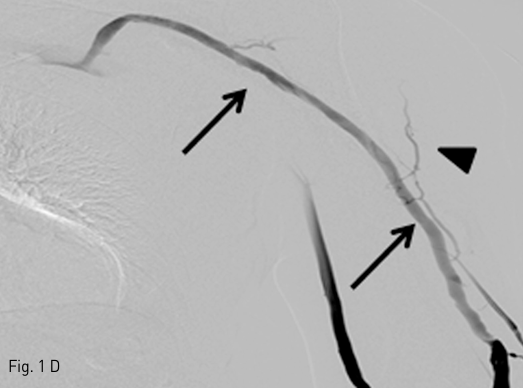

Fig 1D

D. A venography after repeated dilatation with a larger balloon shows complete resolution of the stenosis (arrows) and near disappearance of collateral veins (arrowheads). Note: Basilic vein is visualized by communication with antecubital vein drains into cephalic vein.